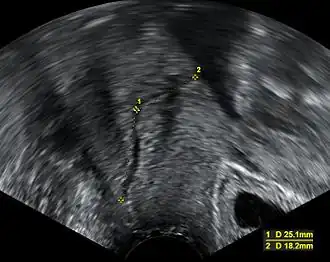

![]() Imagen de ultrasonido midiendo la longitud del cuello uterino en una mujer embarazada con sospecha de insuficiencia cervical | ||

La incompetencia cervical puede ser desafiante y está basada en antecedentes de dilatación cervical no dolorosa normalmente después del primer trimestre y sin contracciones o trabajo de parto y ante la ausencia de otra patología evidente. Además de estos antecedentes, se suele utilizar la longitud cervical medida en el segundo trimestre para identificar el acortamiento cervical con el uso de ultrasonido.[3] Aun así, una corta longitud cervical ha sido pronóstico o marcador de un parto prematuro y no necesariamente de incompetencia cervical. Otras pruebas diagnósticas sugeridas y que aún carecen de validación incluyen la histerosalpingografía e imágenes radiográficas de tracción por balón del cuello uterino, la valoración del patulous cervical con dilatadores de Hegar o Pratt, el uso de una prueba de elasticidad con balón, y uso de graduado de dilatadores cervicales para calcular un índice de resistencia cervical.[1]

Normalmente, el cuello uterino tiene al menos 30 mm de longitud. La definición de incompetencia varía. Aun así, una definición tradicional es aquella con una longitud cervical menor de 25 mm antes o para el momento de las 24 semanas de edad gestacional El riesgo de parto pretermino es inversamente proporcional a la longitud cervical:[4]

- Menos de 25 mm; 18% riesgo de preterm nacimiento

- Menos de 20 mm; 25% riesgo de preterm nacimiento

- Menos de 15 mm; 50% riesgo de preterm nacimiento